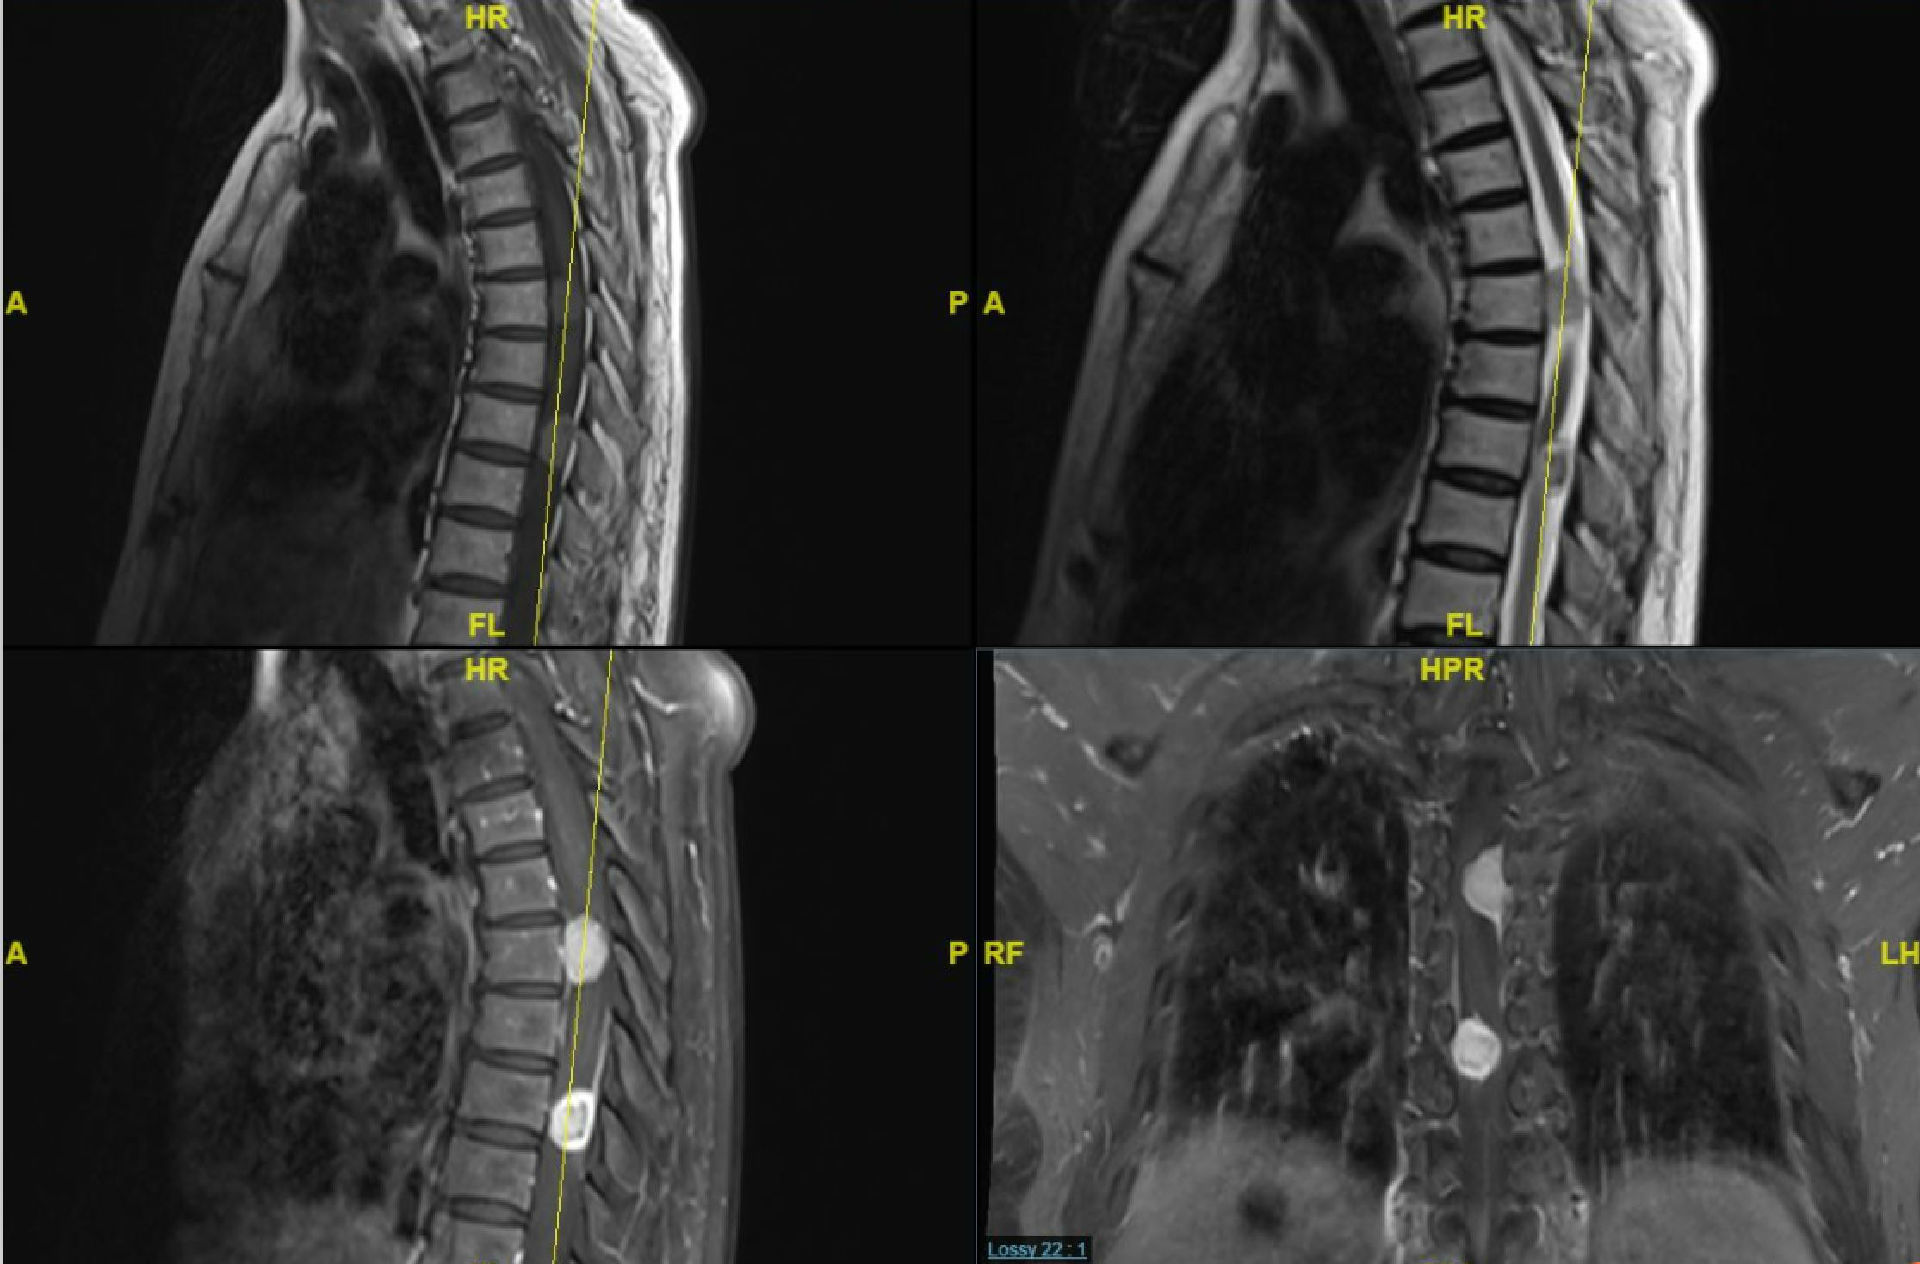

轻轻松松过周末,典型病例发一个,"哑铃征" ,不用鉴别诊断 [病例帖]